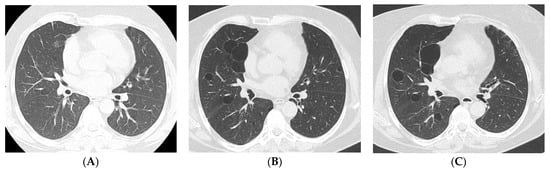

4. Imaging and Histopathology of ILD in pSS

4.1. How Does Radiologic/Histopathologic Pattern Influence the Clinical Picture and Management of pSS-ILD Patients? What Is the Role of Lung Biopsy?